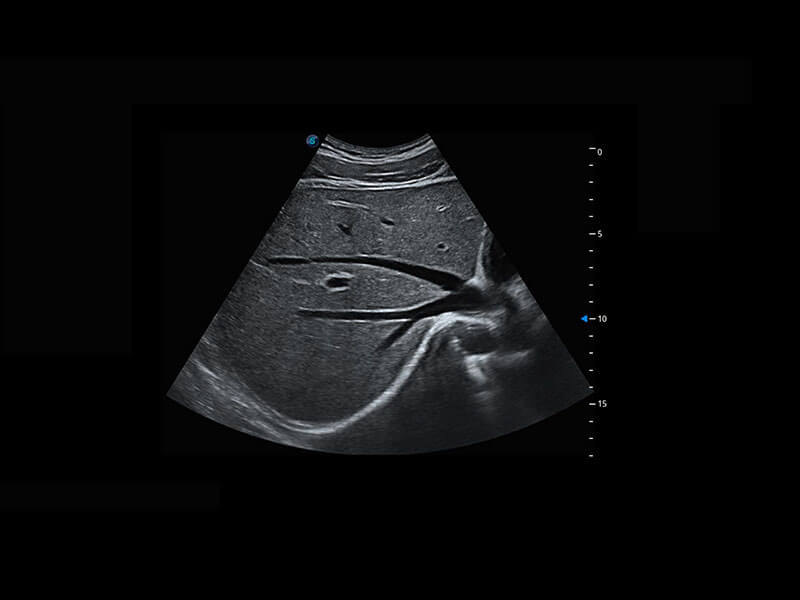

盆底超声

P60为盆底超声检查提供应用方案,多种腔内及腹部容积探头提供从二维、三维到四维的优异图像品质,实时快速三维容积数据获取,专业的测量工具包等人性化设计,为超声医生诊断提供有力保障。

S-Pelvic

能够简化盆底检查的操作流程,可在二维模式及三维成像模式下实现一键自动提取出标准切面、自动识别当前切面、自动测量,提升盆底检查的高效性,同时也能让青年医生快捷的获得准确的检查结果。

Lev.Hiat A-r: 16.33 cm2

Lev.Hiat H-r: 53.70 mm

Lev.Hiat W-r: 43.96 mm

Lt-LUG-r: 24.16 mm

Rt-LUG-r: 19.94 mm